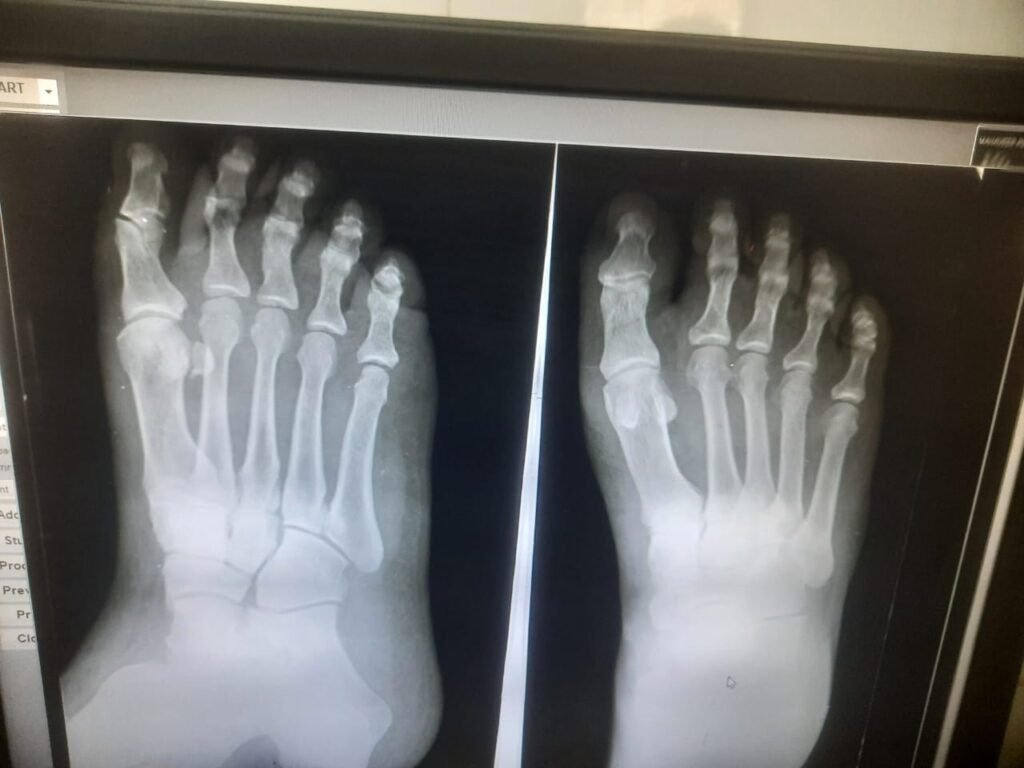

ऐसा ही मामला 31 तारीख का है उसे दिन इटारसी नरेंद्र नगर के निवासी महावीर बड़कुर जी अपनी पुत्री को को रेस्टोरेंट द पार्क में अपनी स्कूटी से छोड़ने जा रहे थे तभी उनकी स्कूटी रोड के मध्य में गैप में फंसने के पश्चात उनका ओवर ब्रिज पर एक्सीडेंट हुआ और स्कूटी भी क्षतिग्रस्त हो गई और ना ही कोई बीमा क्लेम मिला,, जिससे उनको पैरों में फ्रैक्चर अंदरुनी चोटे लगी हैं जिनका इलाज पूर्ण रूप से नहीं मिल पा रहा है और शहर के प्रतिष्ठित चिकित्सालयों ने आयुष्मान कार्ड से इलाज करने से मना कर दिया अब एक मध्यम वर्गीय रोज काम के खाने वाले शहर के नागरिक अपना इलाज शासकीय चिकित्सालय में ही करवा रहे है तत्कालीन स्थिति यह है कि अगर दोषी किसको ठहराया जाएगा तो किसे ,,ब्रिज बनाने वाले ठेकेदार को या पीडब्ल्यूडी के अधिकारी को या इलाज के नाम पर लूटने वाले शहर के प्रतिष्ठित डॉक्टरों को आखिर परेशान तो गरीब आदमी ही होता है जबकि उक्त नागरिक आयुष्मान कार्ड धारक है उसका इलाज शहर के किसी भी बड़े अस्पताल में भी हो सकता है लेकिन स्थिति यह है कि शहर में आयुष्मान के नाम पर जो लूट मची हुई है उसके मध्य नजर भी इलाज नहीं हो पा रहा है